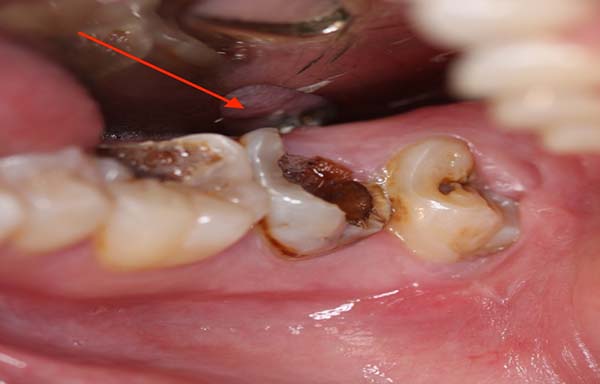

Có nên nhổ răng hàm lớn bị sâu không

Có nên nhổ răng hàm bị sâu không sẽ tùy thuộc vào tình trạng răng sâu thực tế của bạn. Không phải trường hợp răng sâu nào cũng cần thiết phải nhổ bỏ. Bảo tồn là nguyên tắc cơ bản trong điều trị bệnh lý nha khoa. Răng sâu mà đặc biệt là răng hàm một khi bị nhổ răng hàm thì cần thiết phải trồng răng giả càng sớm càng tốt mà tốt nhất là cấy ghép răng implant. Việc trồng răng giả sẽ khá tốn kém mà chức năng ăn nhai, cảm biến thức ăn cũng không thể so sánh được với răng thật.

Trên thực tế, nhổ răng sẽ được nha sỹ chỉ định nhổ bỏ trong hai trường hợp: răng sâu bị viêm nhiễm quá nặng, gây viêm tủy cấp, chân răng bị lung lay và phần thân răng bị vỡ mẻ gần hết không thể bọc sứ bảo tồn và trường hợp thứ 2 là răng bị chấn thương vỡ sát chân răng, mọi biện pháp bảo tồn răng đều không thực hiện được.

Hiện tại, theo những triệu chứng của bạn chúng tôi chưa thể đưa ra một nhận định cụ thể có nên nhổ răng hàm bị sâu hay không. Rất có thể tình trạng răng sâu của bạn đã khá nặng, dẫn tới viêm tủy, tạo nên những cơn đau nhức dữ dội và kéo dài. Trường hợp này cần được thăm khám kỹ lưỡng.

Nếu như răng của bạn đã bị viêm tủy thì điều trị nội nha lấy tủy cần được thực hiện càng sớm càng tốt để bảo tồn răng tối đa. Thao tác lấy tủy có thể được thực hiện sau một lần hẹn với nha sỹ và tiếp theo đó phần răng bị vỡ mẻ cần được phục hồi thân răng và chụp bọc bảo vệ thân răng . Phương pháp này sẽ giúp giữ được cấu trúc thực của răng khỏi tác động bên ngoài bởi một khi răng đã lấy tủy thì độ bền chắc không cao, dễ bị giòn vỡ. Bọc sứ vừa phục hình thẩm mỹ cho răng vừa đảm bảo ăn nhai hoàn toàn bình thường cho bạn.

Khi nào nên nhổ răng sâu là tốt nhất?

Trường hợp răng của bạn không thể bảo tồn được, tình trạng viêm nhiễm đã gây áp xe xương ổ răng thì cần thiết phải nhổ răng sâu để loại trừ nguy cơ ảnh hưởng đến các răng kế bên. Hiện nay, với công nghệ nhổ răng bằng máy siêu âm Piezotome sẽ đảm bảo an toàn cho bạn mà không có biến chứng nào xảy ra.